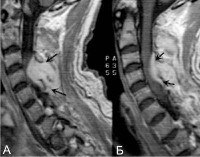

Люмбальную или субокципитальную пункцию совмещают с проведением соответственно восходящей или нисходящей миелографии. Последняя выявляет экстрадуральное (частичное или полное) сдавление спинного мозга, однако малоинформативна в отношении дифференциации вызвавшего компрессию объемного образования, не может различить абсцесс, гематому и опухоль спинного мозга. Наиболее надежным и безопасным способом диагностировать спинальный субдуральный абсцесс является проведение КТ, оптимально - МРТ позвоночника.